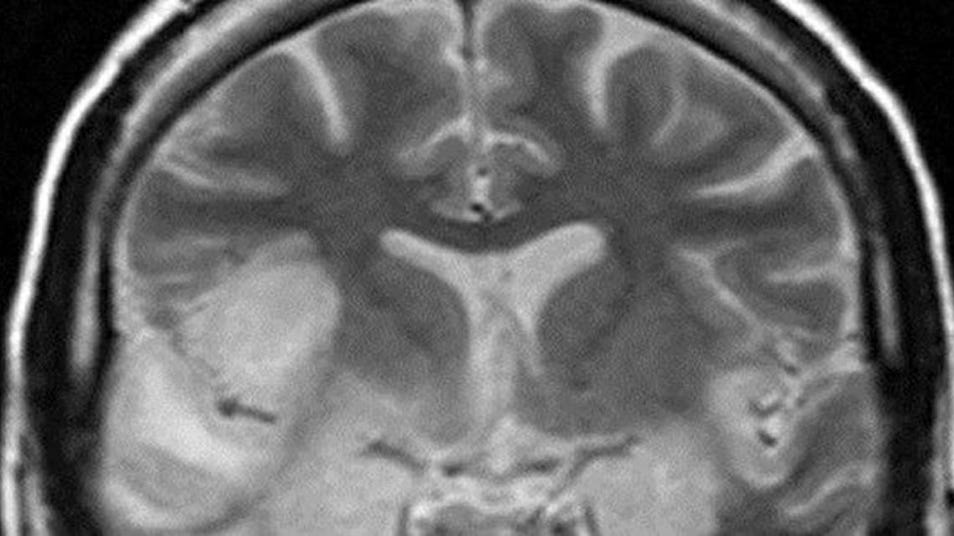

Encephalitis causes inflammation of the brain from infection. In mild cases, sufferers will experience headaches, a fever, convulsions and loss of consciousness. In unusual, chronic cases the encephalitis can become severe enough to cause permanent brain damage or even death.

Header image sourced from http://www.radpod.org/2007/03/24/herpes-simplex-encephalitis/ (Author Dr Laughlin Dawes 2008)